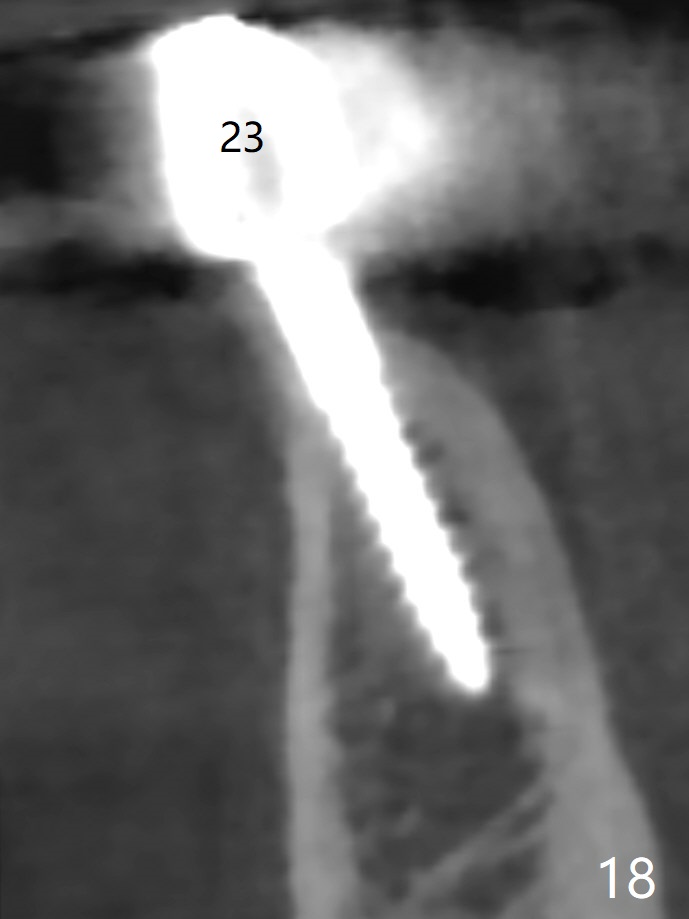

The mesial defect at #27 appears to have been repaired 8 months postop (Fig.8,9 *); there is no bone loss at 1-piece implant sites. The gingival recession seems to remain the same before and after removal of the provisional FPD (Fig.10,11). The bulging abutment at the cervix is less prominent when a straight abutment is used and prepared (Fig.12, 4.5x5.5(5) mm). There is no bone loss at #23, 25 and 27 sites 2.5 years post cementation (Fig.12-15), although the trajectory of the implants could be improved by using surgical guide (Fig.16-18).